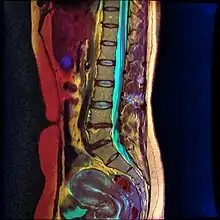

Lumbar sympathetic neurolysis is performed between the L1-L4 vertebrae with separate injections at each vertebra junction. The chemicals used for neurolysis of the nerves cause destructive fibrosis and cause a disruption of the sympathetic ganglia. The vasomotor tone is decreased in the area affected by the neurolysis, which in addition to arteriovenous shunting, create a light pink appearance within the affected area. Lumbar sympathetic neurolysis alters the ischemic rest pain transmission by changing norepinephrine and catecholamine levels or by disturbing afferent fibers. This procedure is mainly used only when other feasible approaches to pain management are unable to be used.[13]

Lumbar sympathetic neurolysis is performed by using absolute alcohol, but other chemicals such as phenol, or other techniques such as radiofrequency or laser ablation have been studied. To aid in the procedure, fluoroscopy or CT guidance is used. Fluoroscopic guidance is the most frequent, giving better real-time monitoring of the needle. The general technique of administering lumbar sympathetic neurolysis involves using three separate needles rather than one because it allows for better longitudinal spread of the chemicals.[13]